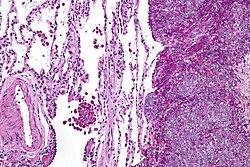

General

- Not a true neoplasm.[8]

- If tumour is understood as a synonym for neoplasm, the name is a misnomer.

- May (clinically) mimic a true neoplasm.

- Due to hyperparathyroidism - usually parathyroid adenoma.

- Usually secondary to chronic renal failure.

Microscopic

Features:

- Fibrosis.

- +/-Giant cells with round to oval nuclei and nucleoli.[10]

- Bone unaffected by tumour - increased numbers of the following:

- Multinucleated cells (osteoclasts).

- Mononuclear cells around the bony trabeculae (osteoblasts).

DDx:

- Giant cell tumour of bone and other giant cell lesions.

Images

- Brown tumour - low mag.jpg

Brown tumour - low mag. (WC)